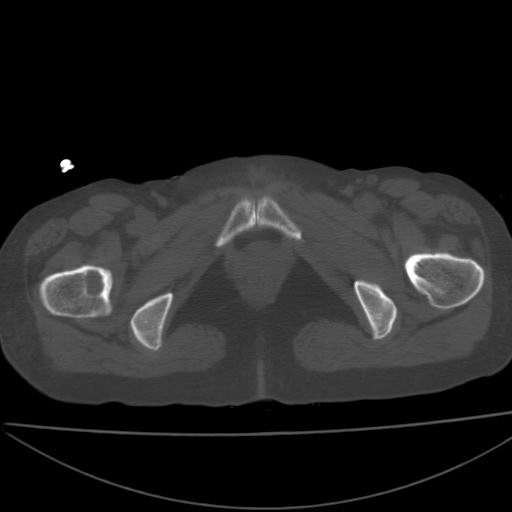

以下是引用xiaoniu在2008-9-6 8:22:00的发言:[br]右侧股骨颈囊性低密度,囊壁边缘硬化,中年妇女,首先考虑:骨囊肿。其次考虑动脉瘤样骨囊肿。[br][br][br][本贴已被 xiaoniu 于 2008-9-6 9:04:54 修改过]